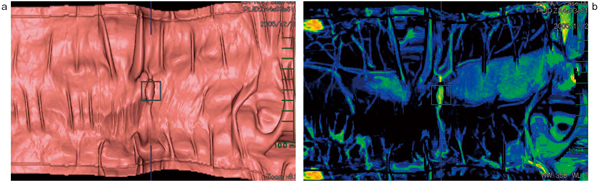

従来より,AZE VirtualPlace 雷神の大腸解析ソフトウェアにも,「展開像(opened image)」として標準搭載されている。最新版では腸管径による補正を施した展開像を選択可能で,腸管の大腸襞や構造物などの歪みが少なく補正された画像を表示可能となっている。腸管拡張の程度に合わせて,腸管径が長い領域は広く,短い領域は狭く展開するため,腫瘍などによる狭窄部は狭窄として明確に認識可能である(図1)。

図1 展開像(opened image)

下行結腸の展開像。桃色は水没により不可視領域となっている領域を表している。同部にて腸管のくびれが認められ(↑),腸管径が狭小化していることが認識できる。

図2 展開像(opened image)

下行結腸の早期大腸がん(0-Ⅱa+Ⅱc,12mm大)。半月ひだ上の結節状隆起として描出されている(○印)。両体位ともに同じ半月ひだ上に結節状隆起があるため,病変の可能性が高いと判断できる。この画像のみで表面の形態を判断するのは困難であるが,ほかの腸管粘膜面と比較して,同部が限局性に隆起していることが容易に検出可能である。